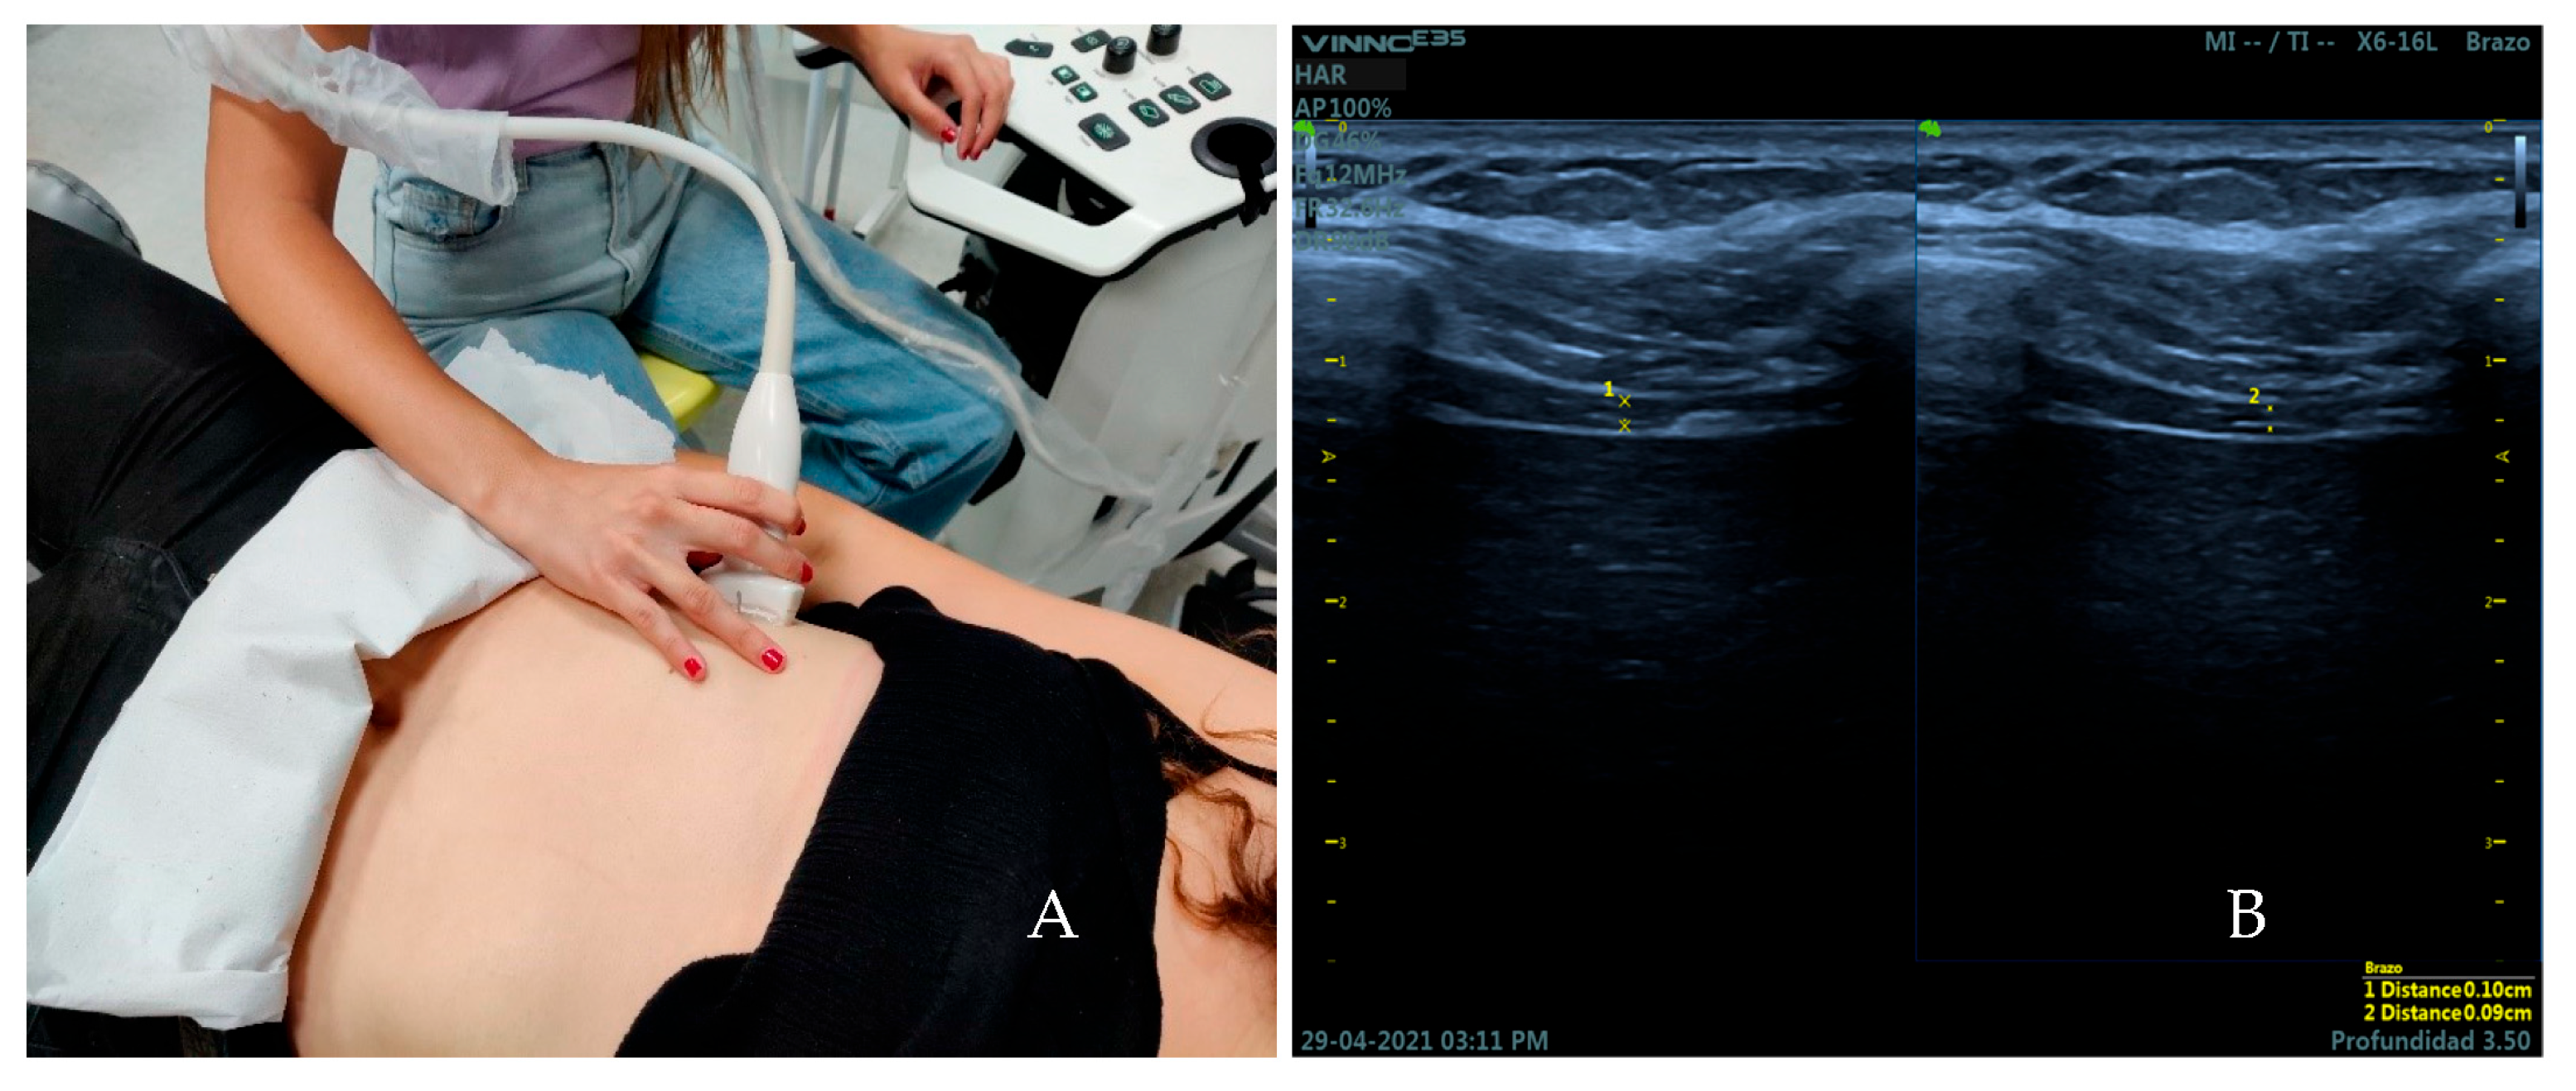

2.4. Measurement Instruments and Examiners

2.5. Measures